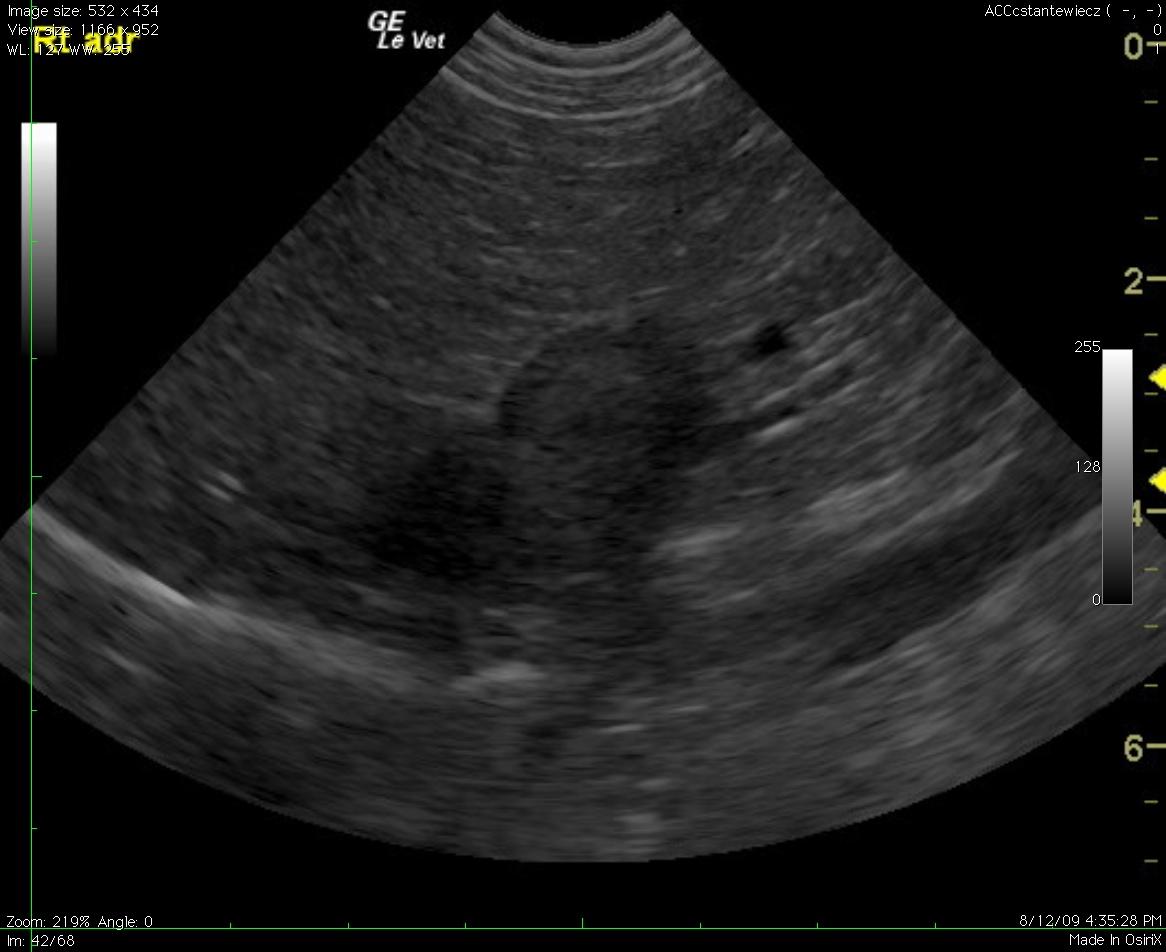

A 13-year-old MN Jack Russell Terrier dog presented for a second opinion with panting, weakness, and anorexia. The physical exam revealed mild gingival pallor and mild tachypnea. Complete blood count revealed strongly regenerative anemia (HCT 22%) with spherocytes, marked polychromasia, anisocytosis, and moderate neutrophilic leukocytosis. Blood chemistry revealed only slight azotemia. In house 4Dx was negative. Blood pressure was 159/98. Urinalysis was pending at the time of the sonogram but urination was reported to be normal.